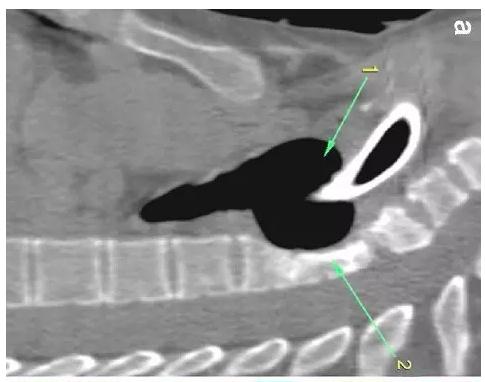

胸部CT顯示氣切套管氣囊周圍氣管擴(kuò)張,胸1-4椎體前部受到侵蝕(下圖a-c)。

患者入住我院前行胸MRI已經(jīng)發(fā)現(xiàn)類似表現(xiàn)(圖d),當(dāng)時診斷為骨髓炎。

下圖箭頭1為氣切套管氣囊緊貼T1-4椎體水平,造成椎體前部受到侵蝕(箭頭2):

作者推測患者骨質(zhì)吸收、骨髓炎與氣切套管氣囊過度膨脹有關(guān),為氣囊過度膨脹造成椎體血流灌注降低所致。在我院住院期間,我們也發(fā)現(xiàn)高氣囊壓力才能防止漏氣。經(jīng)食道內(nèi)鏡檢查未發(fā)現(xiàn)氣管食管瘺。